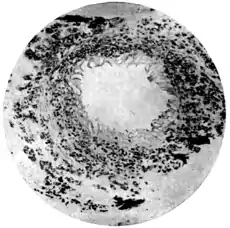

(Microphotograph: Dr. Henderson.) ||Fig. 2.—Eggs of Schistosomum japonicim embedded in walls

of appendix vermiformia.

(Microphotograph: Dr. Kerr.)